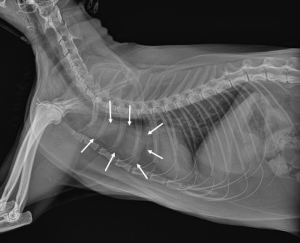

In patients with suspected thoracic disease based on their history and physical examination, veterinarians will recommend further testing, particularly imaging of the thoracic cavity. Radiographs (x-rays) can readily identify a space-occupying mass in the cranial mediastinum. However, there are other structures – most notably lymph nodes – in this location so x-rays can’t provide a definitive diagnosis. Radiographs may also identified fluid in the pleural space, a potential space between the rib cage and the lungs.

A radiograph (x-ray) showed a thymoma in the cranial mediastinum of cat (white arrows). Image Credit: Korean J Vet Res.